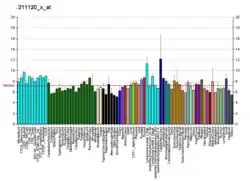

Tissue distribution

ERβ is expressed by many tissues including the uterus,[23] blood monocytes and tissue macrophages, colonic and pulmonary epithelial cells and in prostatic epithelium and in malignant counterparts of these tissues. Also, ERβ is found throughout the brain at different concentrations in different neuron clusters.[24][25] ERβ is also highly expressed in normal breast epithelium, although its expression declines with cancer progression.[26] ERβ is expressed in all subtypes of breast cancer.[27] Controversy regarding ERβ protein expression has hindered study of ERβ, but highly sensitive monoclonal antibodies have been produced and well-validated to address these issues.[28]